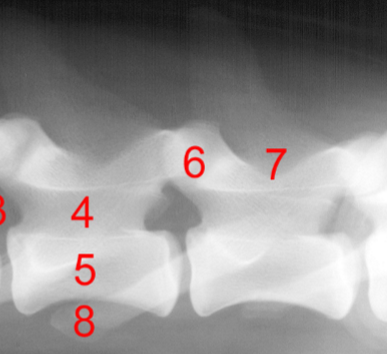

Identify structure 1, 2, 5, 7:

Spinous process

Vertebral body

Vertebral canal

Dorsal laminae

Identify structure 3:

Intervertebral foramen

Identify structure 4:

Pedicle

Identify structure 6:

Articular process

Identify structure 8:

Transvers process